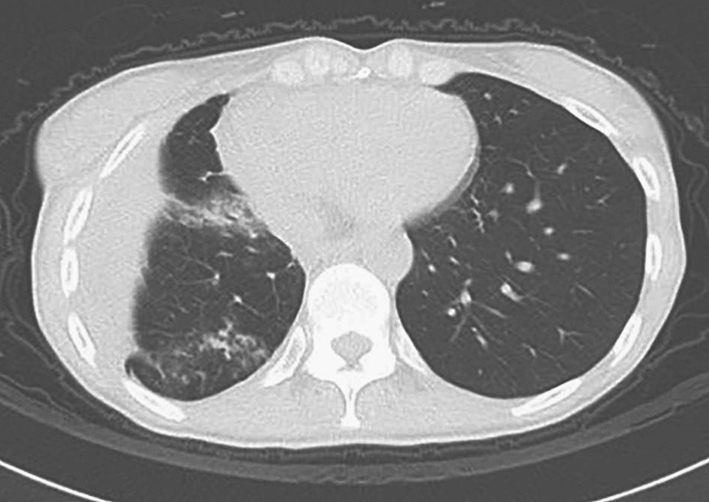

2011年1月患者因发热、咳嗽及咳痰入院,体温最高可达39℃,伴全身肌肉疼痛,以近端肌肉为主,无各系统感染征象,无盗汗、消瘦,无口干、眼干,血培养、痰找抗酸杆菌、痰细菌及真菌培养均阴性,结核分枝杆菌纯蛋白衍生物试验阴性,血结核分枝杆菌-聚合酶链反应(PCR)阴性。支气管灌洗液细胞计数及分类:巨噬细胞20.5%,分叶核细胞66%,淋巴细胞12%,嗜酸性粒细胞1.5%,细胞总数1.07 × 106/ml。支气管肺泡灌洗液涂片:可见大量退变的中性粒细胞,大量肺泡上皮细胞及吞噬细胞,少量红细胞及嗜酸性粒细胞,散在淋巴细胞。类风湿因子、抗环瓜氨酸多肽抗体、抗角蛋白抗体和抗核周因子抗体均阳性,红细胞沉降率、C反应蛋白升高,胸部CT示“右中肺磨玻璃影,机化性肺炎”(图2)。

图2 2011年1月胸部CT示右中肺磨玻璃影,机化性肺炎

先后予莫西沙星、阿奇霉素、头孢他啶、亚胺培南及伊曲康唑规律性抗感染治疗均无效,考虑患者为“类风湿关节炎肺损害、机化性肺炎”,给予甲泼尼龙40mg/d,约2~3天后症状好转,1周后复查胸部CT好转,此后改为口服泼尼松40mg/d,3周后减为35mg/d,并开始加用静脉环磷酰胺,400mg/次,每2周一次。泼尼松减量为35mg/d 1周后(环磷酰胺累计量为400mg),上述症状再次出现,为进一步诊治收入院。既往史、个人史和家族史无特殊。